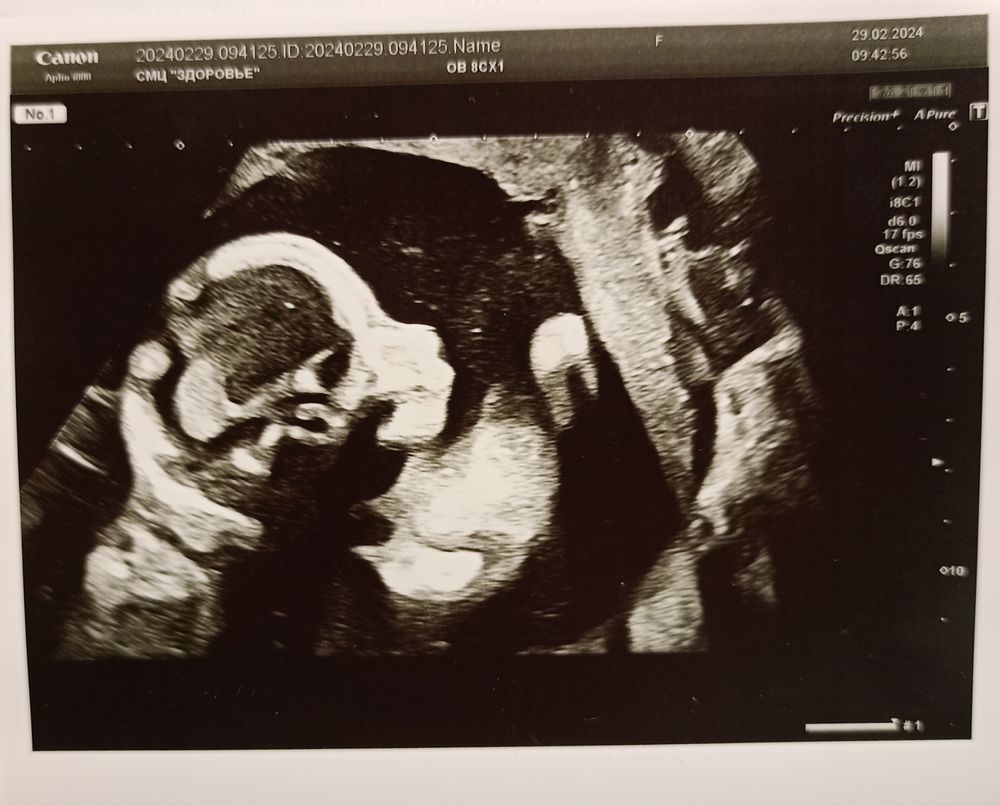

Экватор. Второй скрининг

Сегодня ровно 20 недель по первому скринингу. Малышка растёт и развивается равномерно, сегодня на втором скрининге по замерам соответствует 20н1д. Расчётный вес 340 грамм. С младшим сыном на этом сроке был точно такой же. Всё УЗИ монитор был повернут ко мне - такая упрямая лапотулька - пяточками толкает меня в правый бок, коленки прижаты к носу (нос папин, как у всех😅), повернуть для замеров - то ещё развлечение. Но мы справились😁

С моей стороны тоже по УЗИ всё неплохо - шейка 38 мм, рубец 7 мм. Сдала анализы, там вот могут быть вопросы. Ждëмс.